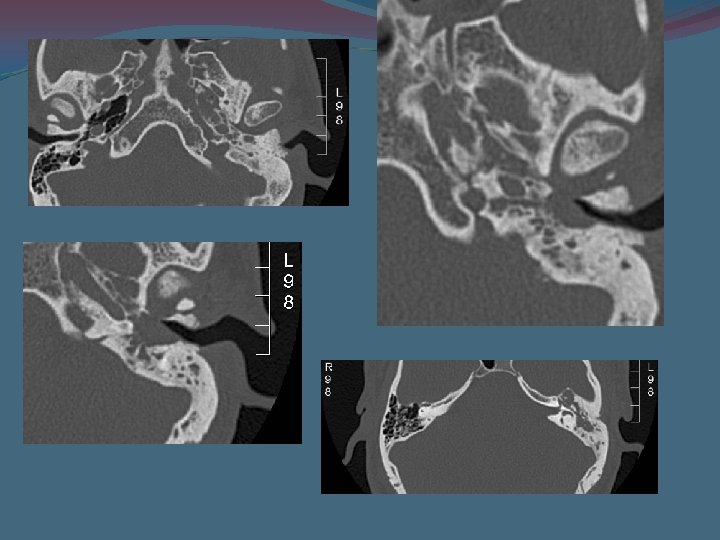

Granuloma de colesterol. Reconstrucciones coronales. ocupación del vertice del peñasco izquierdo asociado a erosión osea

Hallazgos radiológicos En nuestro hospital a los pacientes con sospecha de patología del vértice del peñasco se les realiza TC y RM. A todos los pacientes se les realizo la exploración con TC Toshiba mutidetector de 4 detectores con cortes de 0. 5 mm y reconstrucciones coronales

TC Las lesiones de esta localización pueden ser clasificadas en solidas y quísticas. El granuloma de colesterol es la lesión quística mas frecuente. • La lesión es homogénea de baja atenuación y no esta calcificada, expansiva , erosiva con márgenes bien definidos. • Además se valoro : • la neumatizacion del apex petroso de manera bilateral. • La extensión a fosa cerebral media • La erosión ósea

Se han de describir los hallazgos anatómicos relevantes : el bulbo de la yugular, El recorrido del n. facial, la pared posterior del seno esfenoidal La carótida interna El laberinto óseo